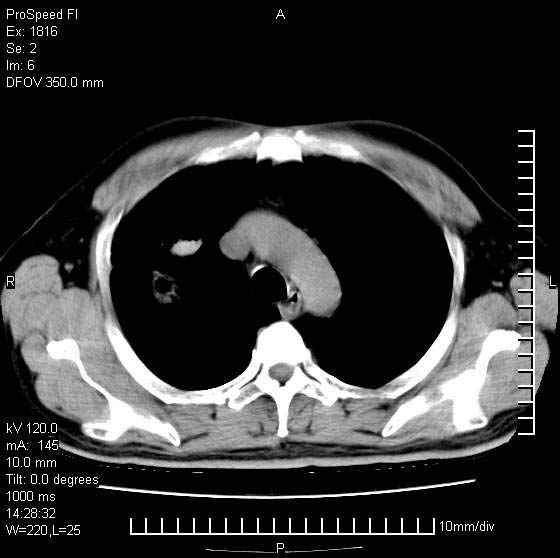

男性,50 ,肺结核9年,咳嗽,胸痛一周。右上肺见一厚壁空洞,周边有点样钙化,胸膜牵拉,洞壁较光整。诊断结核性空洞。有癌性的可能吗? 余肺野无异常,没有上传。

这人应该诊断为肺ca,因为9年的结核密度绝对不是这样!

部分层面见空洞为近似新月形,洞壁内缘尚规整且近肺门侧,周围见索条影、卫星灶,结合病史,首先考虑肺tb可能大。

9年的结核应该呈现多形态病灶,该病例只能见到少许纤维索条影,似乎与结核的演变不太相符。空洞内壁不光整,外侧伴有胸膜粘连,考虑癌性空洞可能性大,期待结果。